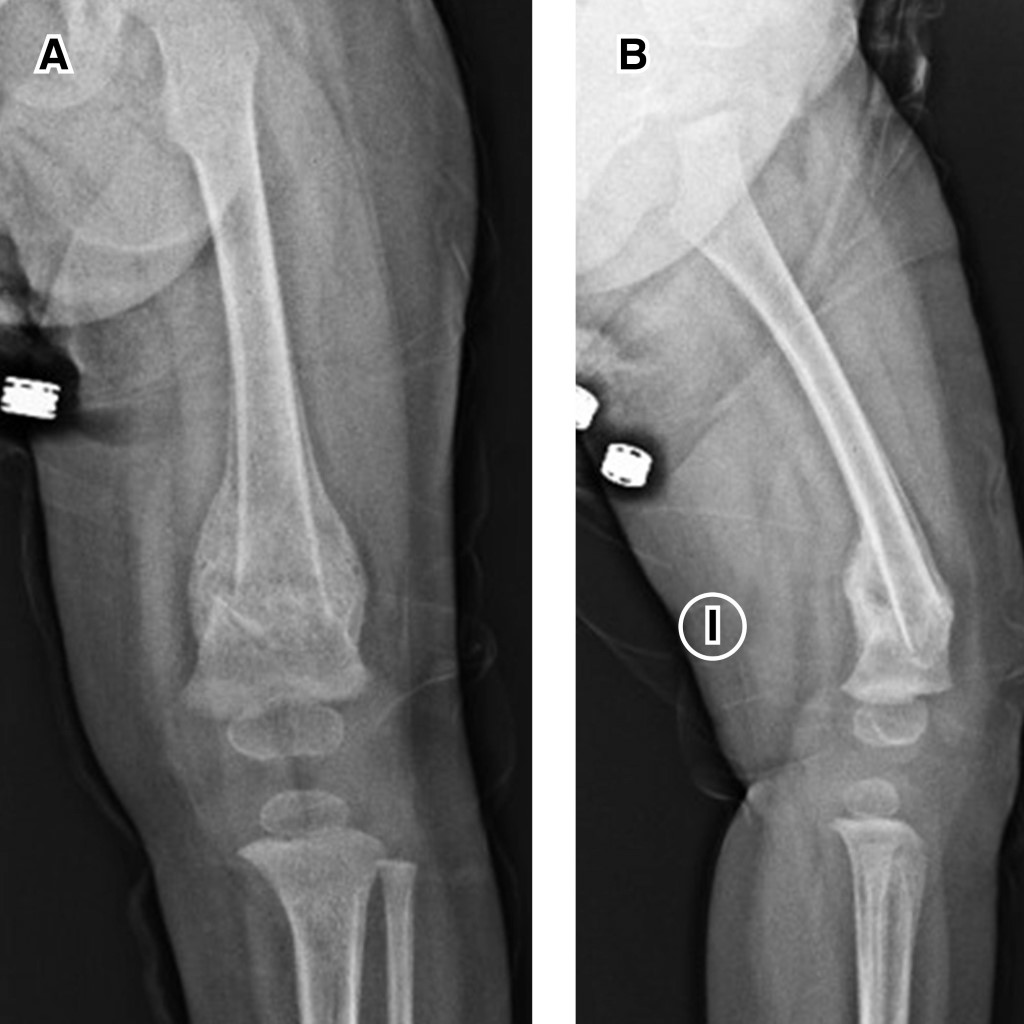

Multiple fractures caused by dystonia and muscular spasms in a patient with mitochondriopathy homozygous ECHS-1 gene mutation

Mitochondriopathies are rare genetic mutations of mitochondrial nuclear DNA that affect primarily the respiratory chain, decreasing the production of cellular ATP. These mutations can be de novo or congenital and have a broad spectrum of clinical presentations. They were first reported in 1958 and four to five new cases are reported per 100,000 births annually. They manifest more frequently as symptoms in organs with high energetic demand and are a diagnostic challenge due to the heterogeneity of clinical manifestations. We present the case of a 16-month-old patient with homozygous deletion mutation of ECHS-1 and glucose-6-phosphate dehydrogenase deficiency. ECHS-1 deficiency has been reported in less than 30 cases worldwide. The deletion manifests in the present case as psychomotor retardation, gastroesophageal reflux, dystonia of difficult control and muscle spasms that have twice caused traction fractures in metaphysis of long leg bones.

Figure 3